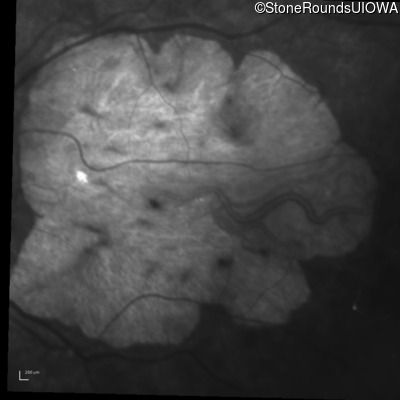

Infrared Fundus Photograph - Right - 20/400 sc

Exemplar